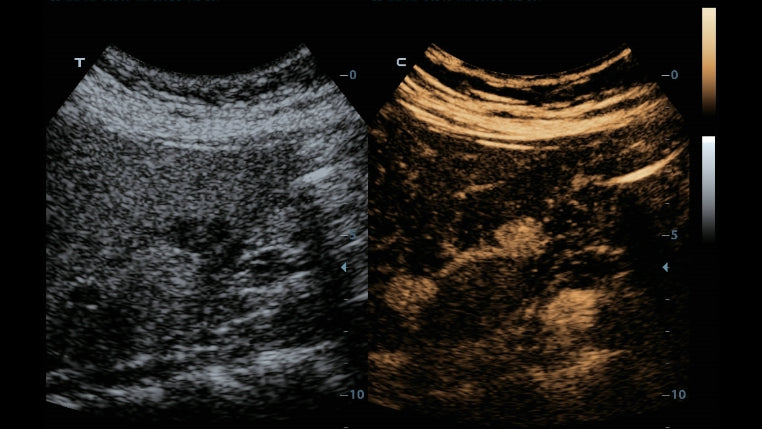

Como una solución de obstetricia, ginecología e imagen general completa, proporciona una interfaz muy robusta e intuitiva. Supera las expectativas de tus rastreos con su sistema de transductores pure crystal